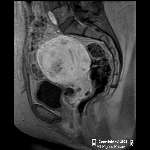

| Prior imaging | oldest & most recent |

| Lines, tubes | E.g. NGT, Dubhoff feeding tube |

| Stones | Nephrolithiasis, cholelithiasis |

| Bones | Ilioishial line, iliopectineal line, arcuate lines, Shenton's arc, coxa vara or valgus, protrusio acetabuli, anterior & posterior rim lines, femoral head, bone texture, joints |

| Mass | |

| Gas | Obstruction, ileus |